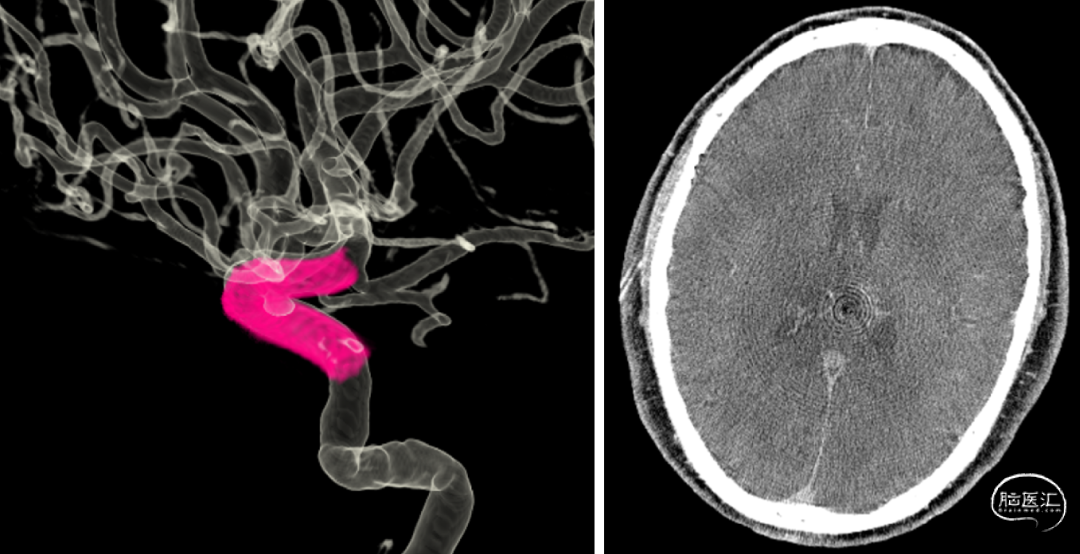

术前检查

DSA:双侧眼段动脉瘤

•DSA手术规划:选择麒麟血流导向装置4.0x20

术后即刻造影